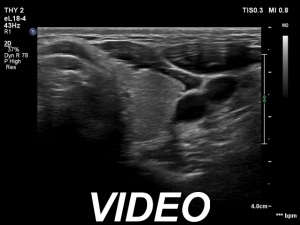

Ultrasonography. The thyroid was echonormal or minimally hypoechogenic. There was an iso/hyperechoic nodule in the right lobe. The lesion had halo and sowed taller-than-wide shape. The vascularity was not specific.

Comments. The nodule is an EU-TIRADS 5 lesion due to the nonparallel orientation.